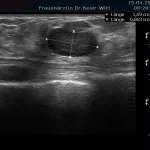

Mammasonographie:

Ultraschall_16